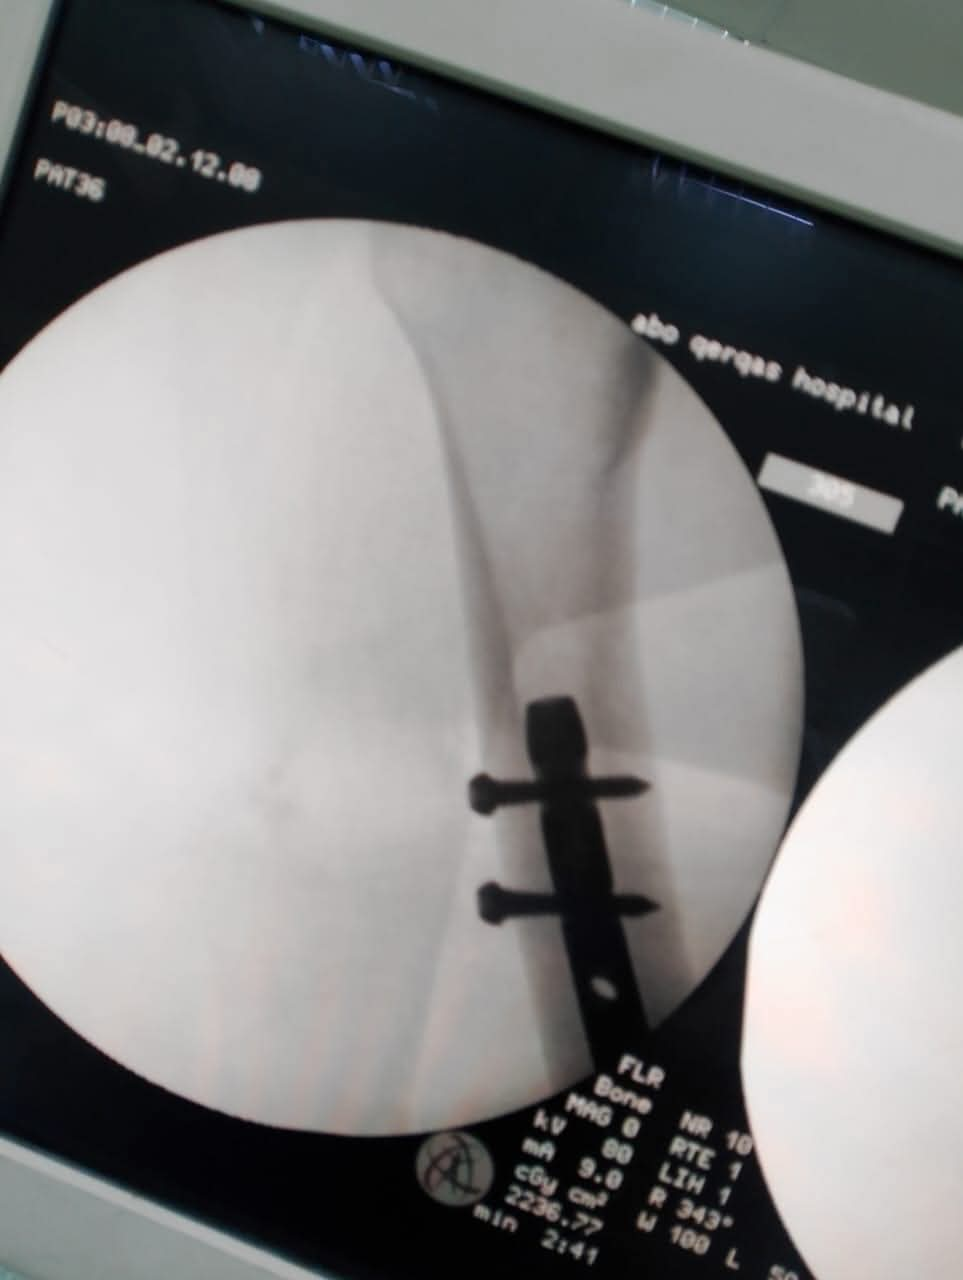

تقنية المسمار النخاعي الارتجاعي (Retrograde Nail):

في خطوة طبية متقدمة، تم التدخل الجراحي وتثبيت الكسر باستخدام "المسمار النخاعي الارتجاعي" عن طريق مفصل الركبة، وهي تقنية حديثة تتطلب مهارة فائقة، خاصة في التعامل مع حالات الأوزان المرتفعة، مما يسمح للمريضة بالتعافي السريع والعودة للحركة في وقت قياسي.